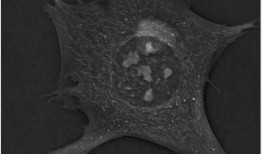

12月19日,瑞士Nanolive公司的Mathieu Frechin及其同事在开放获取的《公共科学...